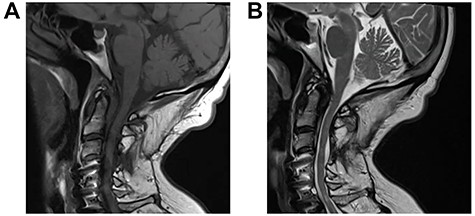

A 64-year-old female status post-two prior spine surgeries presented with recurrent cervical myelopathy. Magnetic resonance imaging (MRI) revealed a 1-cm ventral medullary cyst (Fig. 1A–D), which had enlarged compared with prior imaging. There was significant C1-2 joint arthropathy but no overt instability. She underwent uncomplicated left minimal access far-lateral transcondylar craniotomy for cyst resection. The cyst contained viscous material and was sharply resected, with the exception of the dorsal wall densely adherent to the brainstem. Pathology specimens revealed benign fibroconnective tissue with fibrinous degeneration and focal vascular proliferation (Fig. 2A and B). Immunohistochemical staining for S-100, glial fibrillary acidic protein (GFAP), progesterone receptor (PR), epithelial membrane antigen (EMA) and carcinoembryonic antigen (CEA) was negative; these findings were consistent with a ganglion cyst. Her pain resolved and strength and balance improved post-operatively. Repeat imaging 4 months post-operation demonstrated gross total cyst resection with resolution of the bulbar syrinx and reconstitution of appropriate ventral medullary anatomy (Fig. 3A and B).

MRI findings of a ventral atlantoaxial degenerative cyst with an associated medullary syrinx; axial T1-weighted pre-contrast (A), axial T1-weighted post-contrast (B), axial T2-weighted (C) and sagittal T2-weighted (D) images demonstrate an approximately 1 × 1 cm T1-isointense, T2-hyperintense, rim-enhancing cyst at C1-2 compressing the ventral medulla with an associated a fluid-filled medullary syrinx.